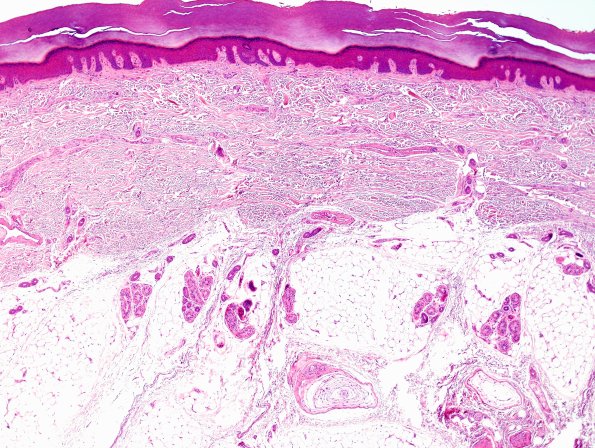

Washington University Experience | METABOLIC | Neuronal Ceroid Lipofuscinosis (NCL) | 2A1 NCL (Kuf's Dz, Case 2) Skin 1.jpg

2A1-3 Many patients in our practice are tested for NCL during life using skin biopsies (most are negative), We examined the skin in this patient with known Kufs disease at autopsy. This series of H&E stained images is surprisingly normal in appearance. (H&E)